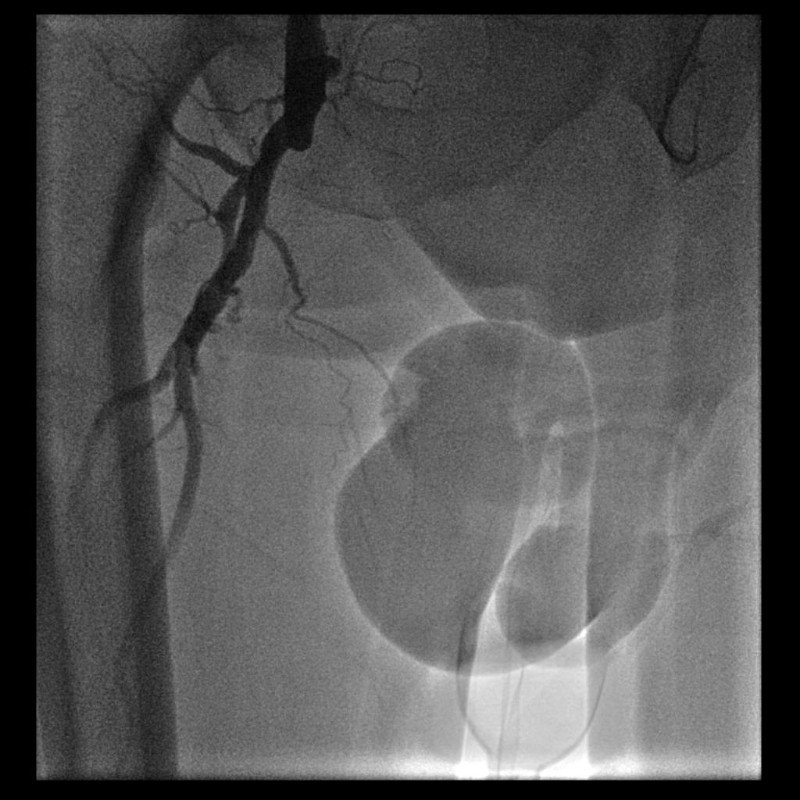

Bacak ağrısı şikayeti ile başvuran hastanın MR Anjiyosunda bacak ana damarının tam tıkalı olduğu görüldü. Daha öncesinde bacak ağrısı nedeni ile üç kez bel fıtığı ameliyatı olan ve dördüncü kez bel fıtığı ameliyatı önerilen hastanın şikayetinin asıl nedeninin Bacak Damar Tıkanıklığı olduğu anlaşıldı. Stent uygulaması ile damardaki darlık açıldı. Hastanın takiplerinde bacak ağrısının ve yürüme sorununun tamamı ile geçtiği görüldü.